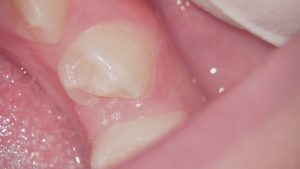

左は処置前、右は処置後。突起の周りをプラスチック樹脂で補強する処置になります。

補強した上、突起を2~3ヶ月毎にわずかに低く削っていくと、徐々に神経も小さくなって突起が折れるリスクが軽減します。